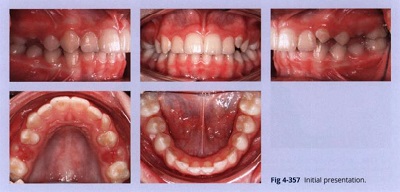

Bệnh nhân nữ 11 tuổi này có khớp cắn loại II, răng hàm trên và dưới chen chúc nhẹ, lệch đường giữa nhẹ, và cắn sâu. Răng nanh hàm trên của bệnh nhân và răng hàm nhỏ vẫn đang mọc (Hình 4-357).